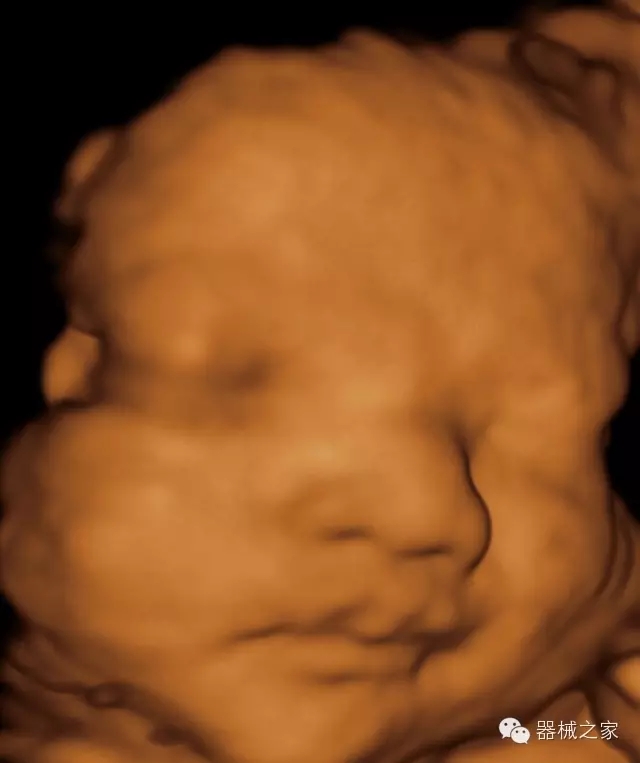

臨床圖片賞析

·完整的3D/4D臨床應(yīng)用,STIC, MCUT 和Auto NT等滿足產(chǎn)科所有應(yīng)用;

·更高的HQ羊膜腔鏡成像技術(shù)精細(xì)觀察每一個(gè)暗區(qū)細(xì)節(jié);

·智能的觸摸屏界面,能任意角度方位旋轉(zhuǎn)3D圖像,以及注釋快速標(biāo)記,提供直觀與便捷的操作,提高了工作效率;

·高效3D/4D成像技術(shù):高速的4D幀頻,豐富的3D成像模式,智能斷層切片功能;